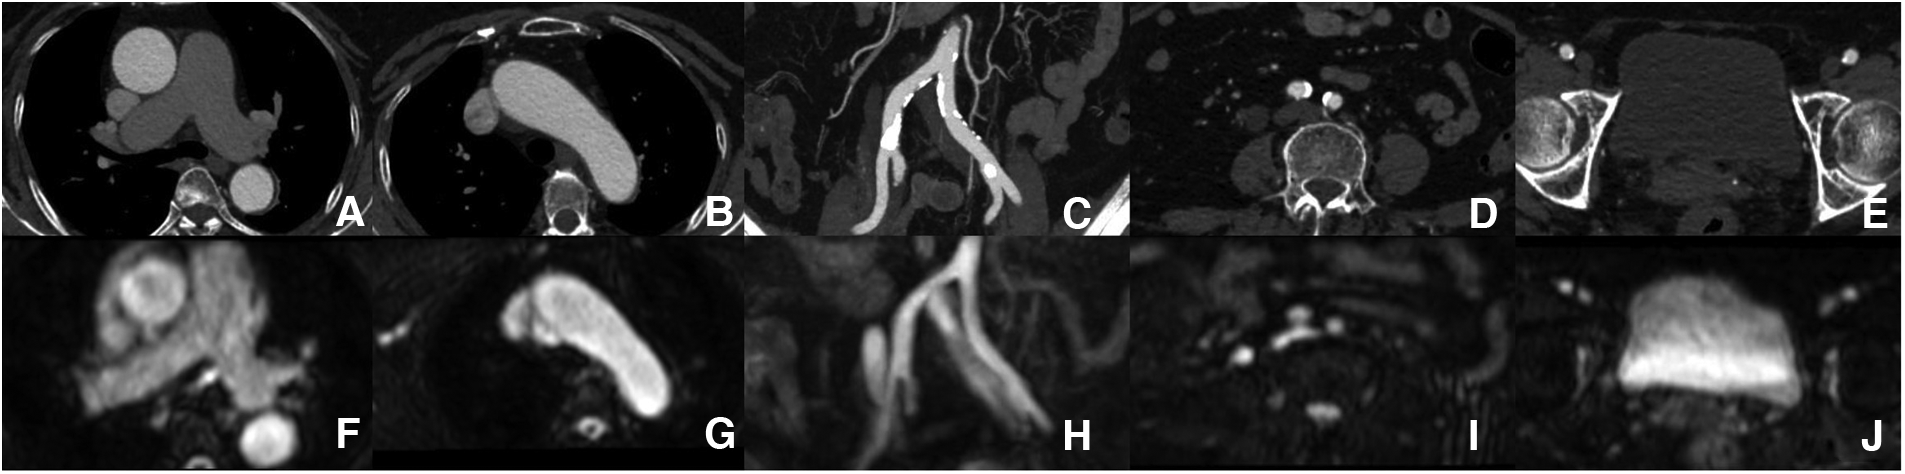

Aorta and iliofemoral access measurements. Each part of the aorta and iliofemoral arteries were measured by both modalities [(A–E) ACTA vs. (F–J) REACT].

No significant differences were found in the perimeter, area, and average diameters of the annular ring and in coronary ostial heights between 3D whole-heart MRI and CCTA data. The diameters of the ascending thoracic aorta (37 ± 4.6 mm vs. 37.7 ± 5.2 mm, p = 0.085), descending thoracic aorta (24.3 ± 2.8 mm vs. 24.3 ± 2.8 mm, p = 0.832), abdominal aorta (20.9 ± 2.5 mm vs. 20.8 ± 2.5 mm, p = 0.602), bilateral common iliac arteries (right: 8.36 ± 1.44 mm vs. 8.42 ± 1.27 mm, p = 0.590; left: 8.61 ± 1.71 mm vs. 8.86 ± 1.46 mm, p = 0.050), and bilateral femoral arteries (right: 6.77 ± 1.06 mm vs. 6.87 ± 1.00 mm, p = 0.157; left: 6.75 ± 1.02 mm vs. 6.90 ± 0.80 mm, p = 0.142) showed no significant differences between REACT and ACTA data. Excellent agreement was found in aortic root dimensions and aorta and iliofemoral access route measurements for both modalities (Tables 2,3, Figures 2–4).

Diameters of the aorta and iliofemoral arteries (11): The diameters of the ascending and descending thoracic aortas, abdominal aorta, and bilateral iliofemoral arteries were measured by REACT and ACTA. In this study, the diameter of the ascending thoracic aorta was measured at the level up to 40 mm from the aortic valve, the descending thoracic aorta was measured at the level of trachea bifurcation, and the abdominal aorta was measured at the level of the celiac track artery. The minimum diameters of common iliac arteries and external iliac arteries were measured, and femoral arteries were measured at the proximal segment.